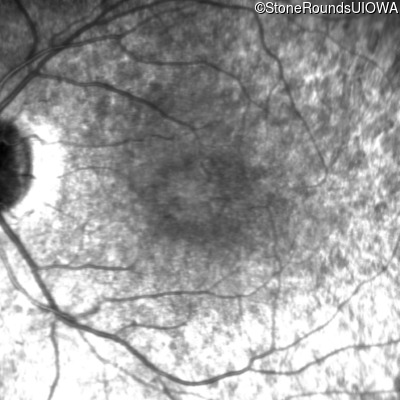

Age at visit: 7 years

This 7 year old girl has had very poor vision in dim light and slightly subnormal acuity her entire life.

Age at visit: 7 years (Visit 2)

Age at visit: 8 years

Age at visit: 9 years

Age at visit: 10 years

Age at visit: 12 years

Age at visit: 13 years

Age at visit: 14 years

Age at visit: 15 years

Age at visit: 16 years

Age at visit: 17 years

Age at visit: 19 years

Age at visit: 21 years